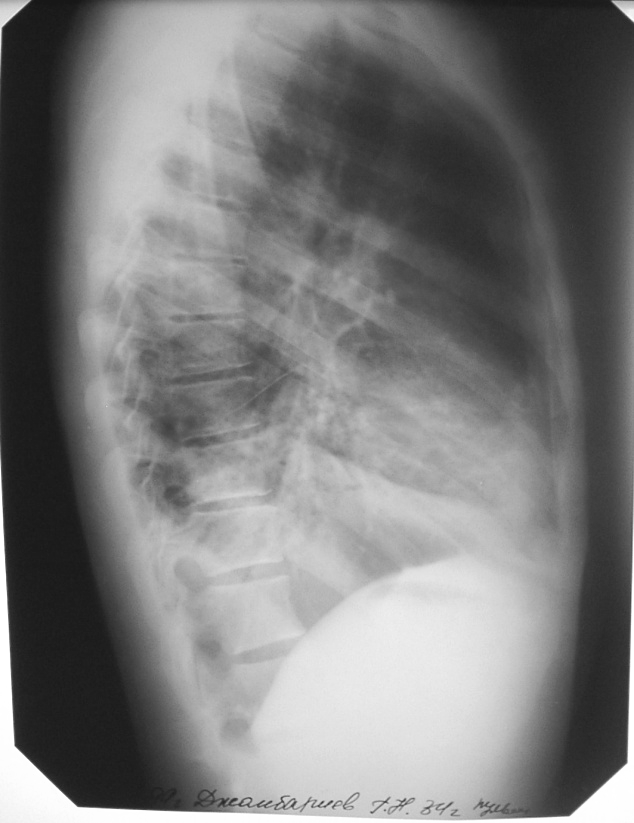

Что такое малоконтрастная рентгенограмма органов грудной клетки